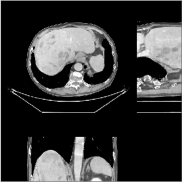

We reconstructed the abdomen volume from low-dose helical CT data. With an initialization of zeros, we ran the PWLS-EP algorithm with and for iterations with subsets for the mA and mA scans, respectively. For PWLS-ULTRA, we chose for the mA scan, for the mA scan, and ran it for outer iterations. The other parameter settings and the transform were the same as those used for the chest scan.

Fig.Β 10 shows the reconstructions (shown for the central axial, sagittal, and coronal planes in the 3D volume) for PWLS-EP and PWLS-ULTRA with patch-based weights () from low-dose abdomen scans. For the sagittal and coronal planes, we show the central out of axial slices. The supplement provides PWLS-EP reconstructions with different regularization strengths. The PWLS-ULTRA reconstructions in Fig.Β 10 have reduced noise as well as higher resolution, better structural details and shaper image edges than the PWLS-EP results. These results are further example of the potential performance of the proposed PWLS-ULTRA method in clinical settings.